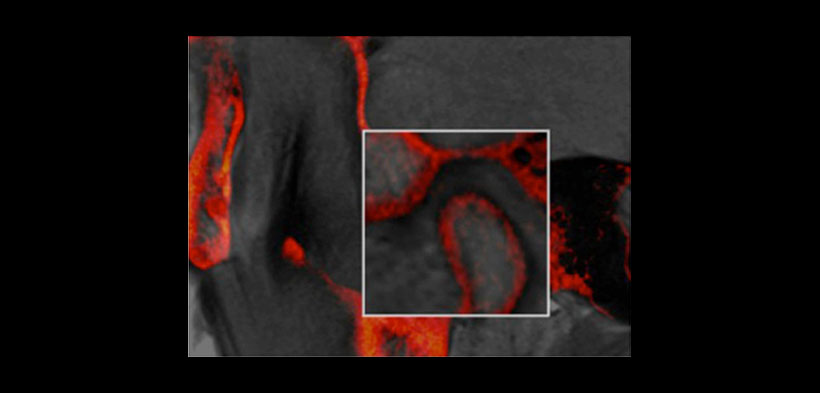

Fig. 2. Imagen sagital de la fusión de imágenes (RM-CBCT) de la articulación temporomandibular derecha (ATM), muestra excelentes bordes de las superficies articulares de la ATM (cabeza del cóndilo, fosa glenoidea y la eminencia articular) se superponen a 1 píxel.